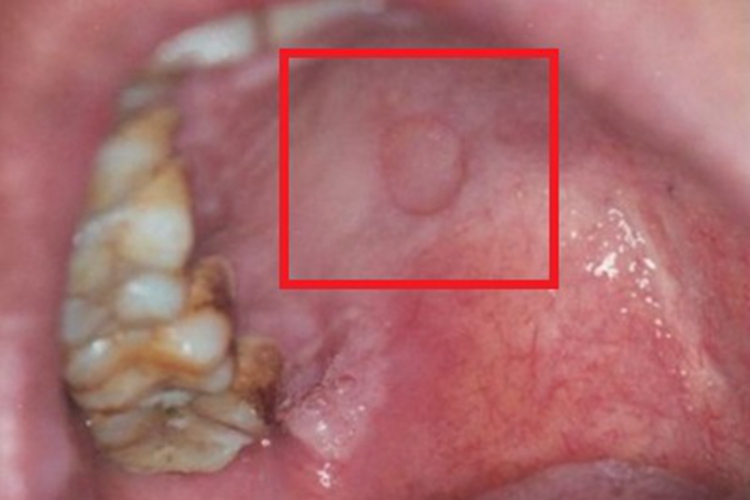

女性梅毒可发生在口腔,表现为圆形、类圆形或不规则形的白斑,大小不等,表面光滑,边界清楚,周边微隆起,触之较硬,一般没有疼痛。